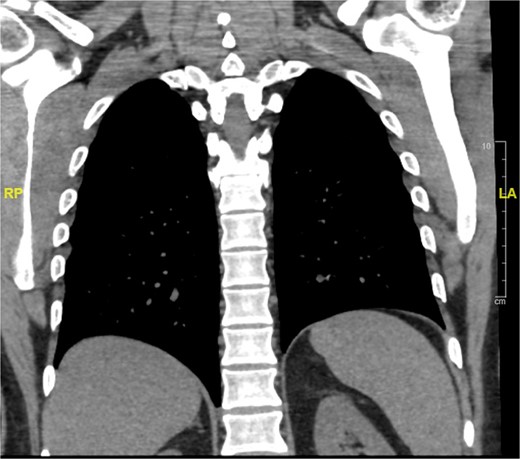

To exclude the possibility of distant metastasis, CT of the chest, abdomen, and pelvis (CAP) was performed. The scan showed a few small pulmonary nodules, the largest measuring 0.4 cm. The patient was referred to the pulmonology department for further evaluation. The patient will repeat imaging in four months to monitor the nodule (Fig. 5).

Stable bilateral small pulmonary nodules seen within the lower lobes of the lung.